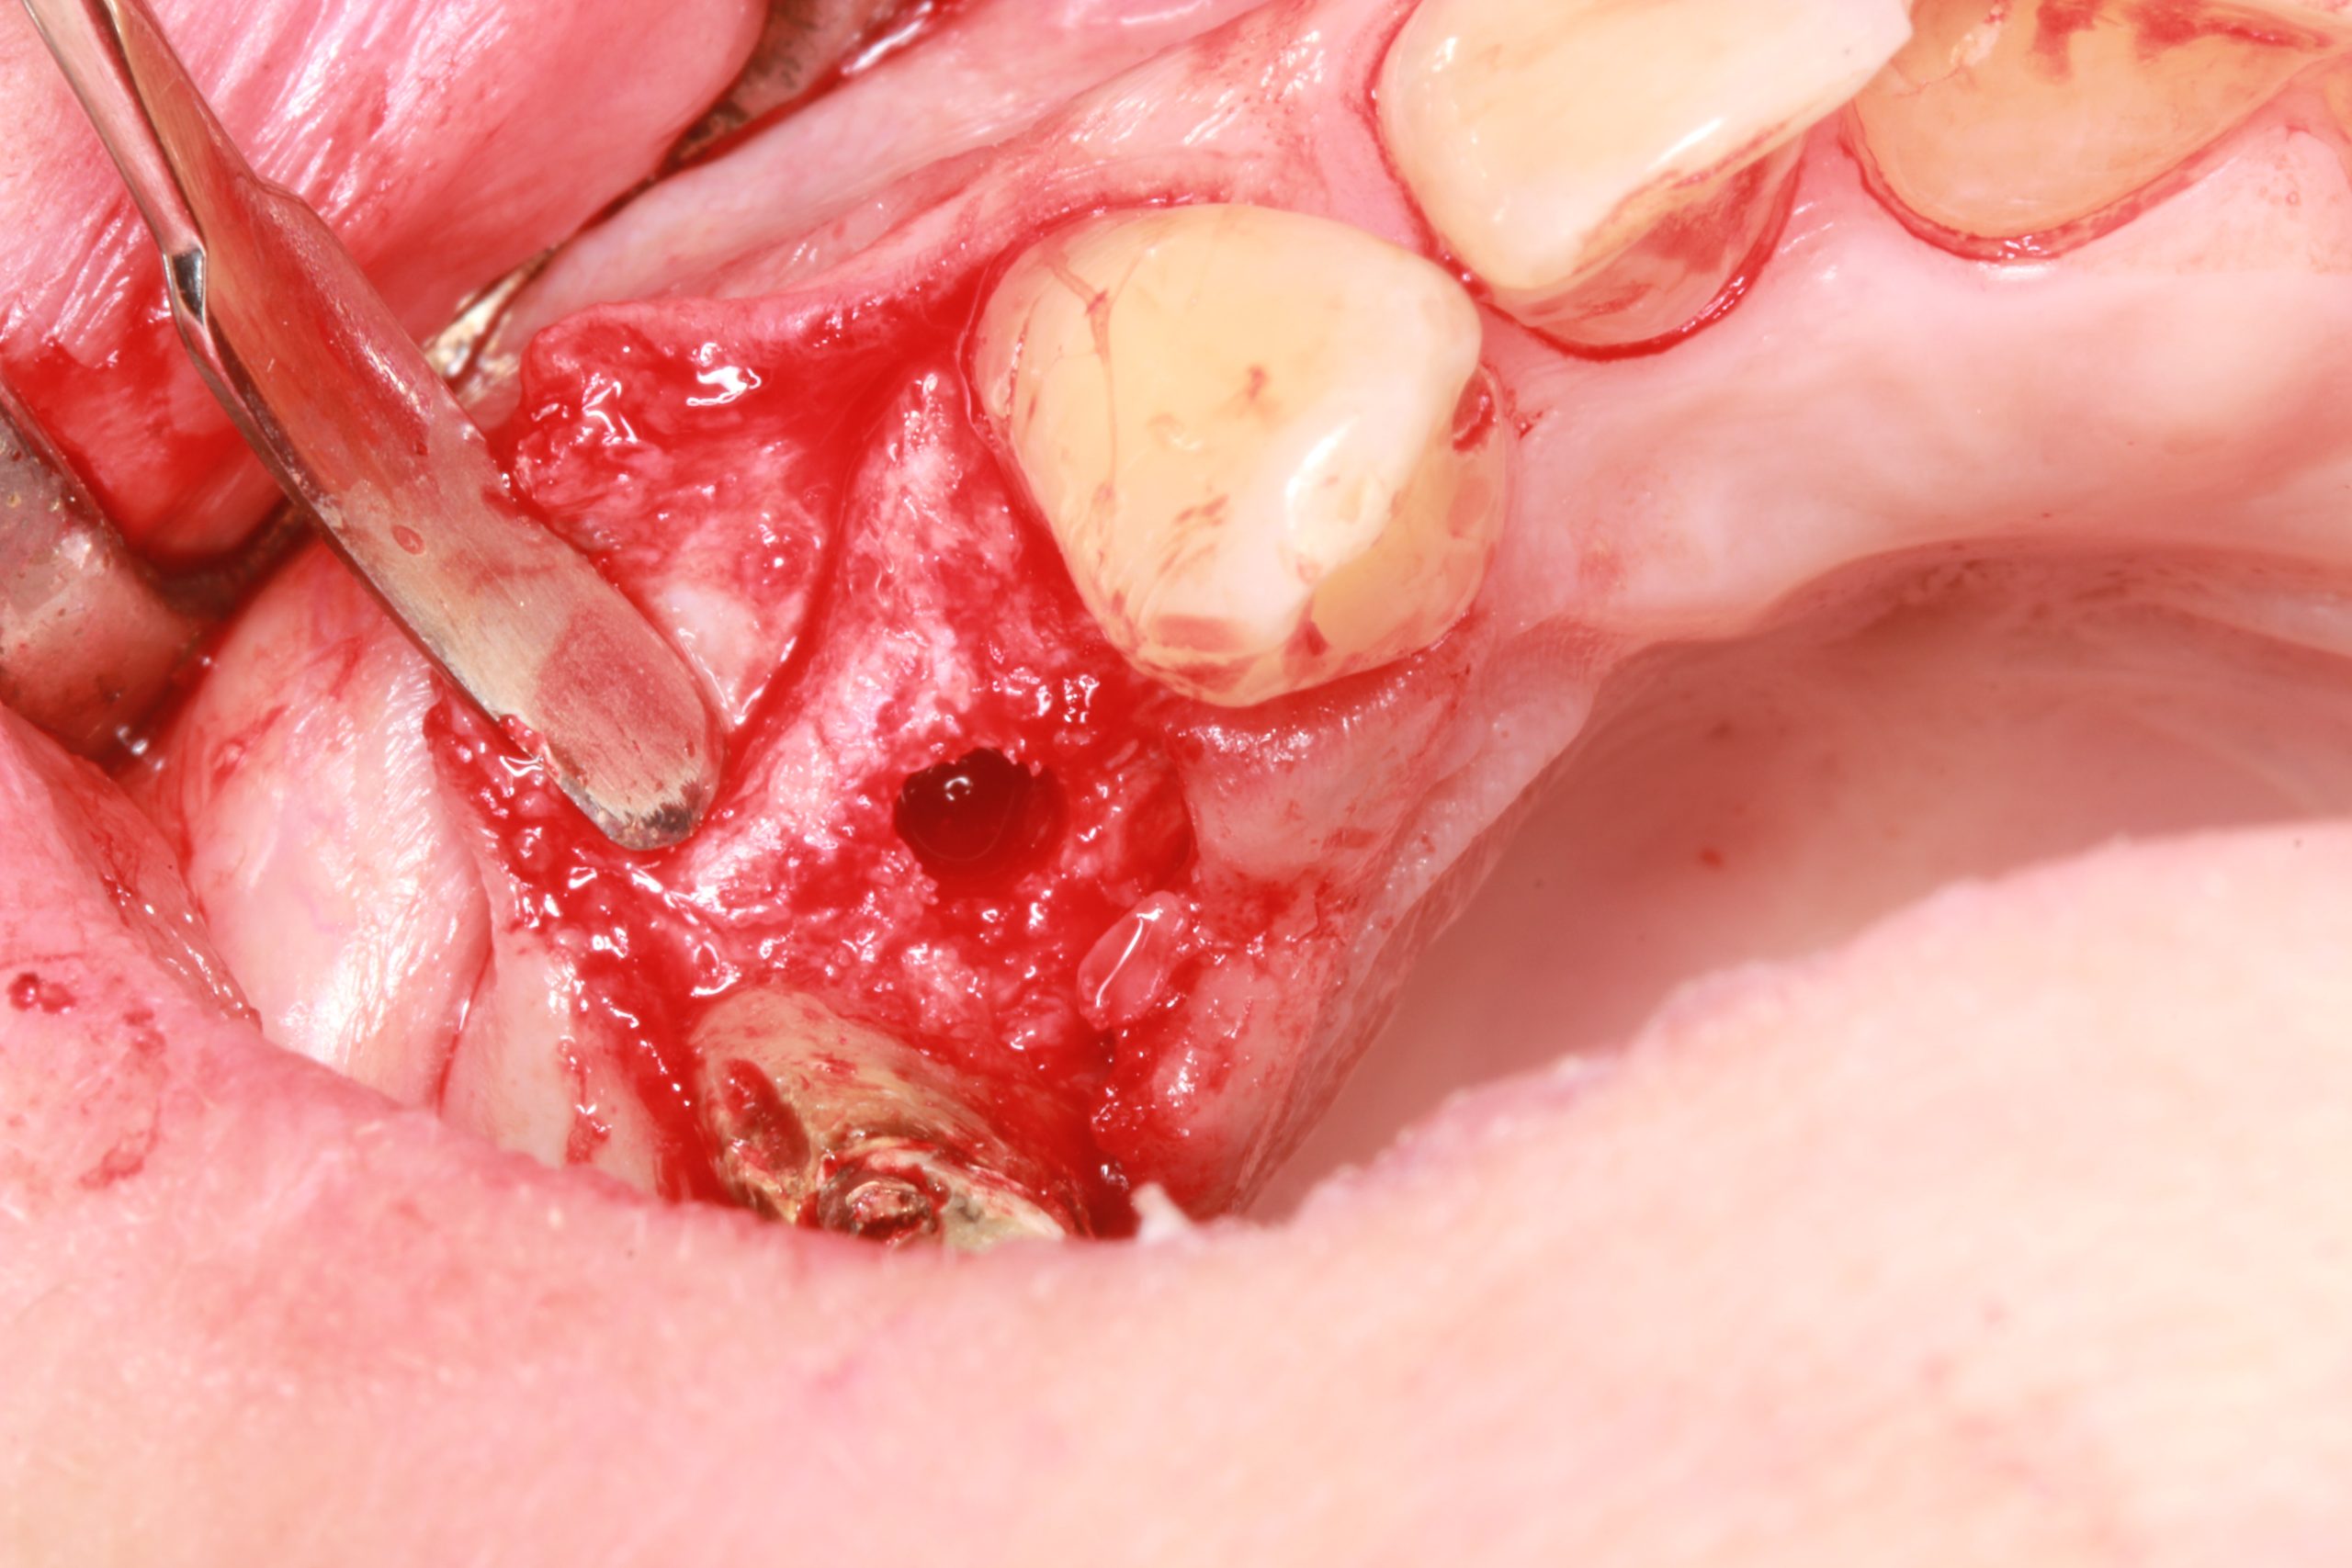

Die Präparation des Implantatbetts wurde mittels der Chirurgieschablone mit dem geführten Bohrer BioniQ® S2.9 unter Überwachung des Systems für die aktive Navigation DENACAM angefangen.

Die Schablone wurde entfernt und die Präparation wurde mit den konventionellen Instrumenten unter Verwendung des Systems für die aktive Navigation vollendet. Die genaue Einhaltung der geplanten Implantatposition wurde auf dem Bildschirm kontrolliert.